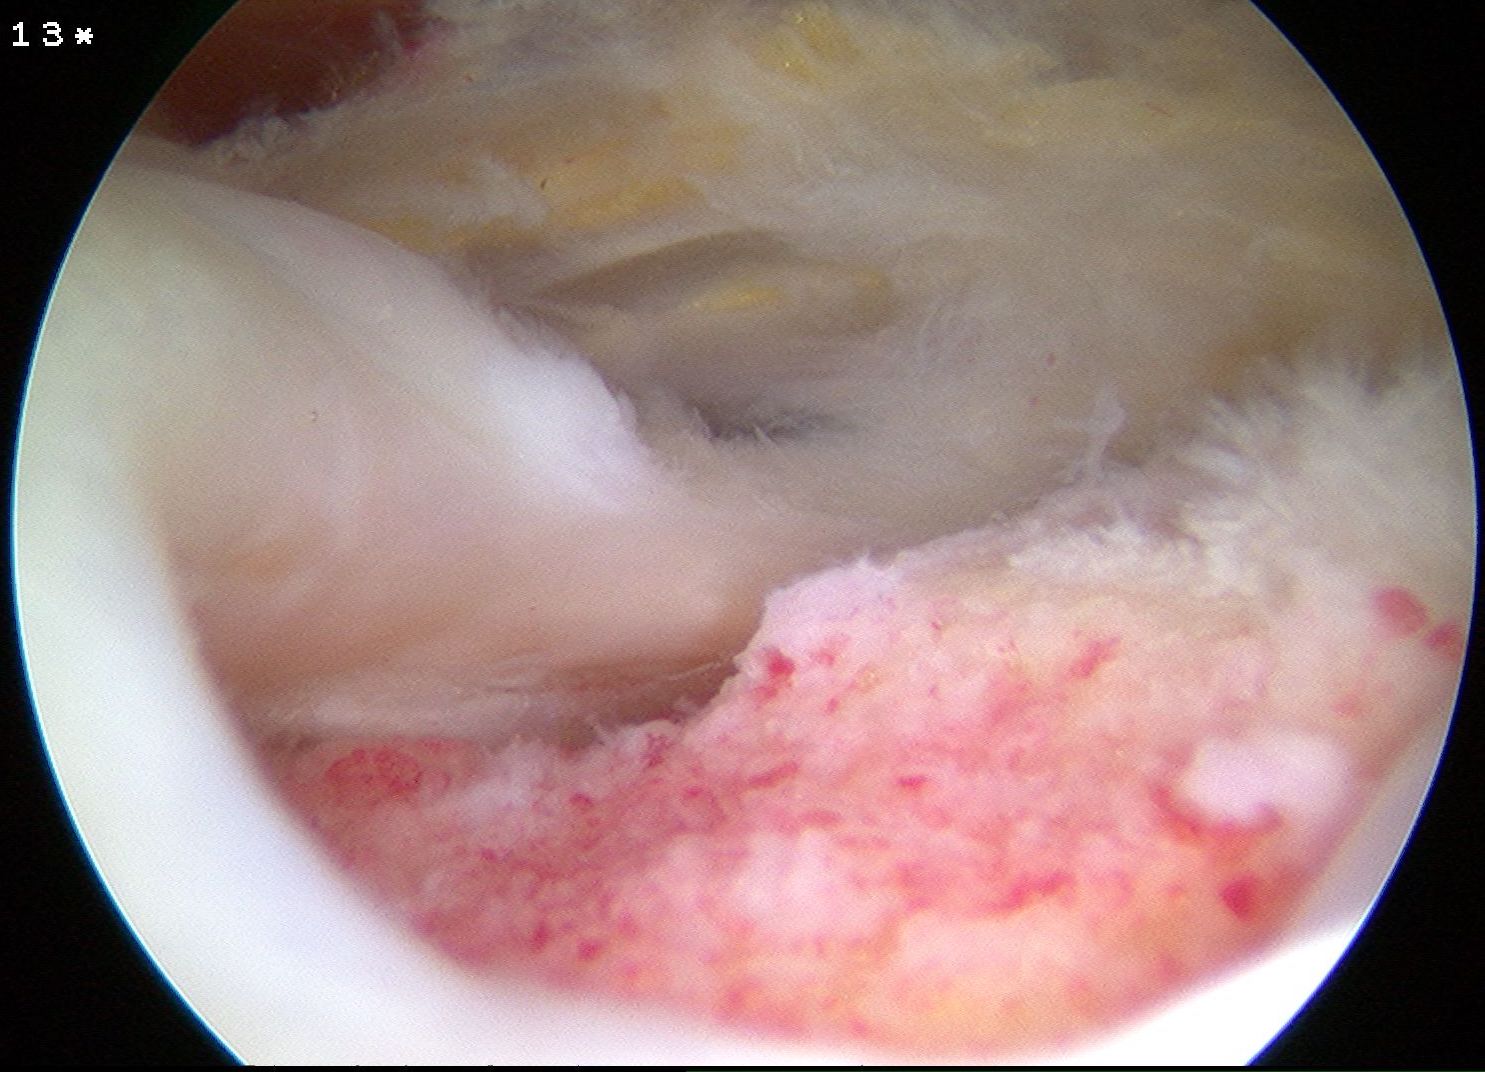

Subacromial joint

- bursectomy for visualization

- acromioplasty if acromial spur

- debride footprint to bleeding bone

- +/- microfracture / K wire of footprint / marrow stimulation

Assess tear